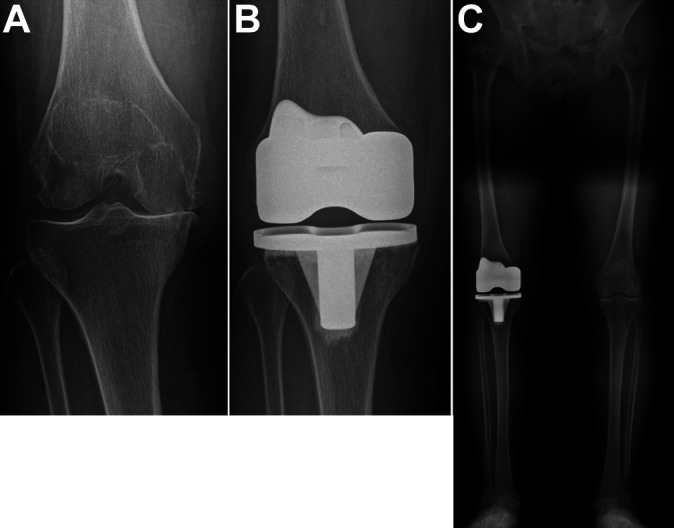

Nella maggior parte dei casi consiste nella sostituzione delle superfici articolari del ginocchio: la porzione distale del femore e quella prossimale della tibia.

Per mezzo di precisi tagli anatomici operati dal chirurgo, al posto delle superfici articolari vengono posizionate delle componenti in leghe metalliche biocompatibili, frapposte da un inserto in polietilene che permette lo scorrimento tra le componenti stesse. (1)

Dal punto di vista dell’anatomia articolare esistono principalmente due tipi di protesi al ginocchio:

- quella monocompartimentale, o parziale: che prevede la sostituzione della sola componente mediale (o interna) o laterale (o esterna) di tibia e femore;

- quella bicompartimentale o totale: dove vengono sostituite completamente le superfici articolari di tibia e femore e, all’occorrenza, può venire rivestito anche il versante articolare della rotula (in questo caso è corretto parlare di protesi tricompartimentale) (1);